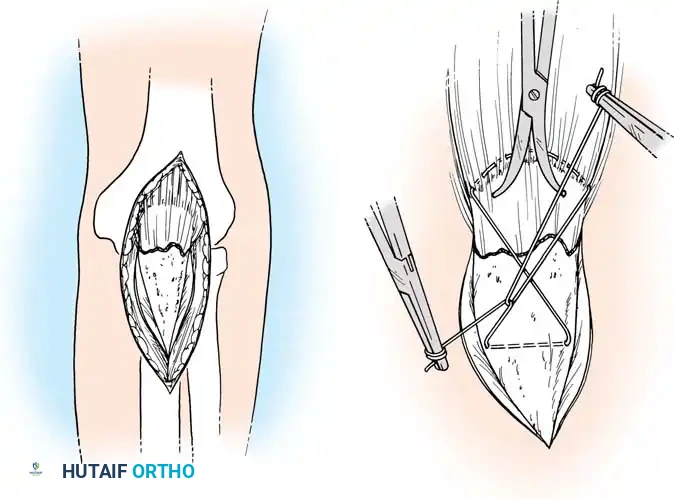

3. Excision of the Proximal Fragment

Excision is indicated primarily for elderly, low-demand patients with severe comminution where stable osteosynthesis is impossible, or when the articular surface cannot be congruously restored. Up to 50% of the olecranon can be excised without compromising elbow stability, provided the coronoid process and collateral ligaments remain intact.

🔪 Surgical Technique: Excision and Triceps Advancement

- Fragment Removal: Carefully dissect the comminuted fragments from the triceps tendon, preserving as much tendon length as possible.

- Joint Debridement: Inspect the joint and remove all intra-articular debris.

- Bone Preparation: Smooth the remaining proximal end of the ulna. If the midportion of the olecranon is comminuted but the proximal tip is intact, the central comminuted segment can be excised (Barford technique). The osteotomies must be directed accurately along the radius of the trochlear curve to reconstitute a smoothly curved notch.

- Triceps Advancement: Drill two or three longitudinal holes through the remaining proximal ulna. Pass heavy non-absorbable sutures (e.g., #2 or #5 FiberWire) through the triceps tendon using a Krackow stitch, pass them through the drill holes, and tie them securely over the posterior ulnar cortex with the elbow in 30 degrees of flexion.

Fig. 54-57 Technique of excision of central one third of olecranon process (Barford, 1972). It is critical to err by making the radius of the notch too large, rather than too small.